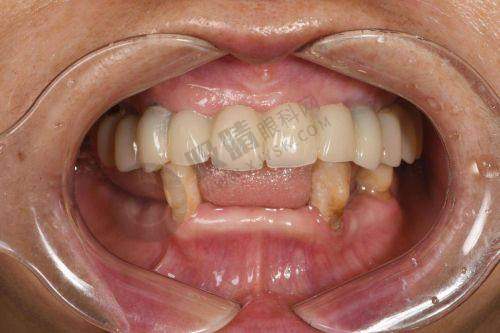

骨干医生团队更是实力雄厚,拥有口腔治疗医生6名,副医生12名,其中包括博士研究生导师4名,硕士研究生导师8名。以刘习强医生为例,他是口腔颌面外科的骨干医生主事,医学博士毕业生,口腔颌面外科博士研究生导师,还是教育部新世纪的非凡人才之一。他主持过多项自然科学基金项目,发表40多篇学术论文,参编6本教材著作,擅长各类口腔治疗、口腔颌面整形、美容种植牙手术、微创拔牙手术、牙齿矫正手术等。

医院的热门医疗项目也备受关注,包括微创种植牙、青少年牙齿矫正、口腔根管治疗、牙周基础治疗、牙齿敏感治疗、复杂的牙髓病治疗、全瓷牙美白、美白贴面手术等,为患者提供了多样化的治疗选择。